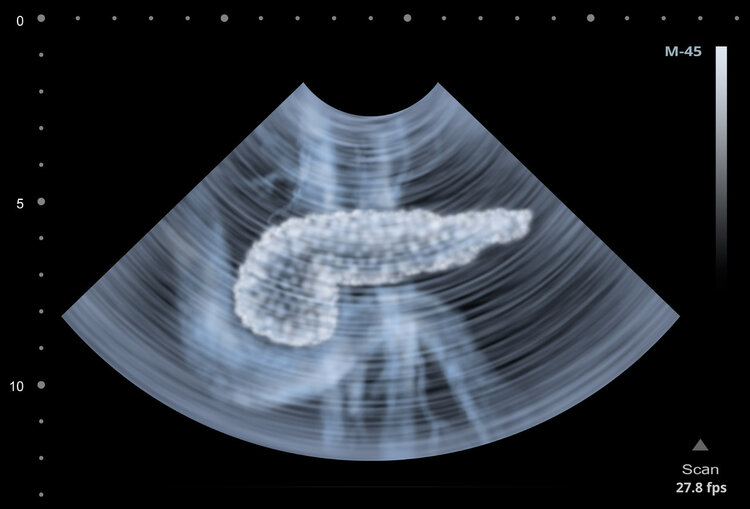

1、超声检查:常用方法之一,操作简单,不损坏身体,可很好地显示胰腺内部结构,看胆道内是否梗塞。但由于视野比较小,容易受胃部、肠道内的气体以及体型的影响,所以需结合CT做进一步诊断。